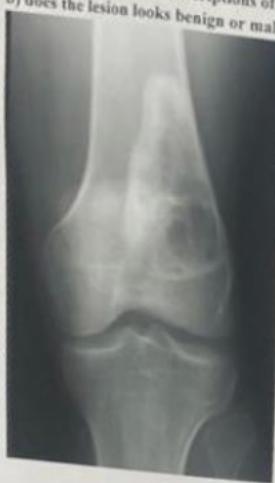

| Look | Compare both limbs, Skin, Muscle bulk, bony landmarks, hair distribution | Assess symmetry, signs of trauma, inflammation, muscle atrophy, structural changes | Visual examples - Skin, Muscle, Bone, Joint: ![]() ![]() ![]() ![]() ![]() ![]() | Swelling, scars, discoloration, hair changes, muscle wasting, bony protrusions, angulation, redness |

| Move | Active first: General screening for pain, then passive | Assess patient’s voluntary range of motion and pain patterns | Limited or painful active movement indicating muscle or joint involvement | |

| Flexion & Extension (Normal: Extension: 0° → Flexion: 140°) | Quantify the knee’s range of motion | Extension: Flexion: ![]() | Reduced or excessive range of motion; “lacks X degrees of extension” | |

| Effusion: Milking OR Patellar Tap | Detect presence and severity of joint fluid | Large Effusion visible: Patellar Tap (Balloting): ![]() | Minimal effusion: Fluid demonstrable with “milking.” Mild effusion: Fluid pushed away, then reappears. Moderate effusion: Fluid not pushed away. Moderate/severe effusion: Positive patellar tap (balloting). | |